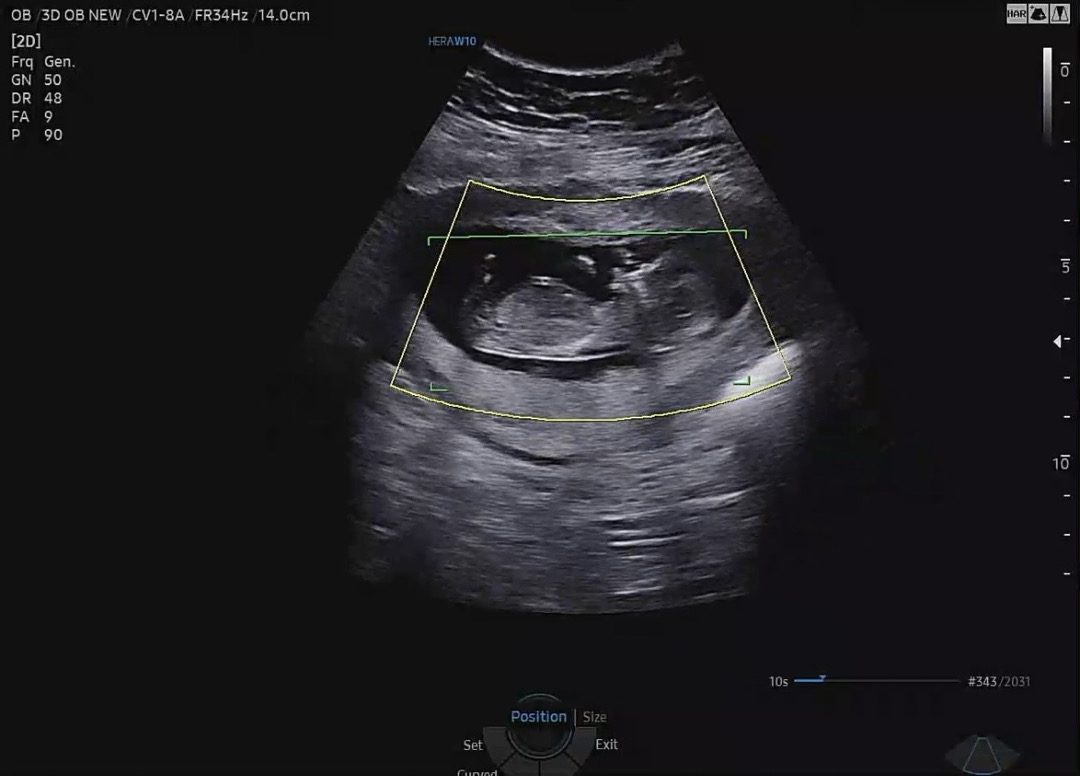

성별 봐주세요~

12주 각도법알려주세요~